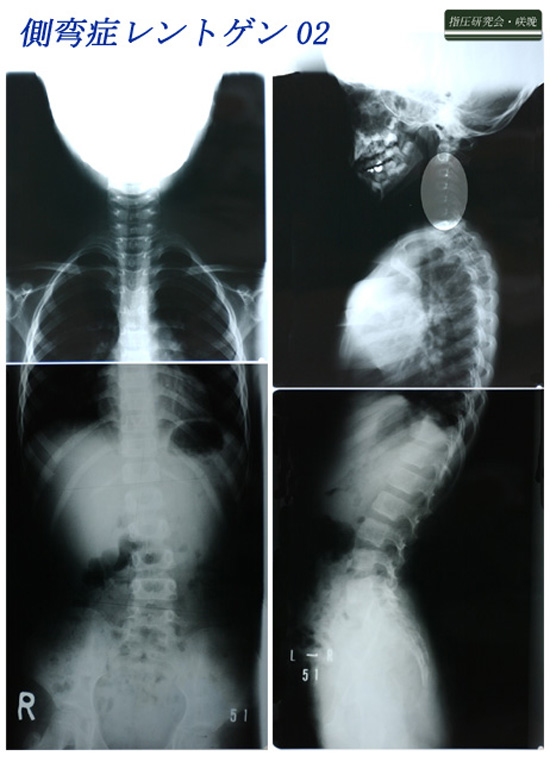

脊柱側弯症レントゲン02

脊柱側弯症の前面と側面からのレントゲンを紹介します。

脊柱側弯症の治療に立体的筋肉バランスの調整法は欠かせません。